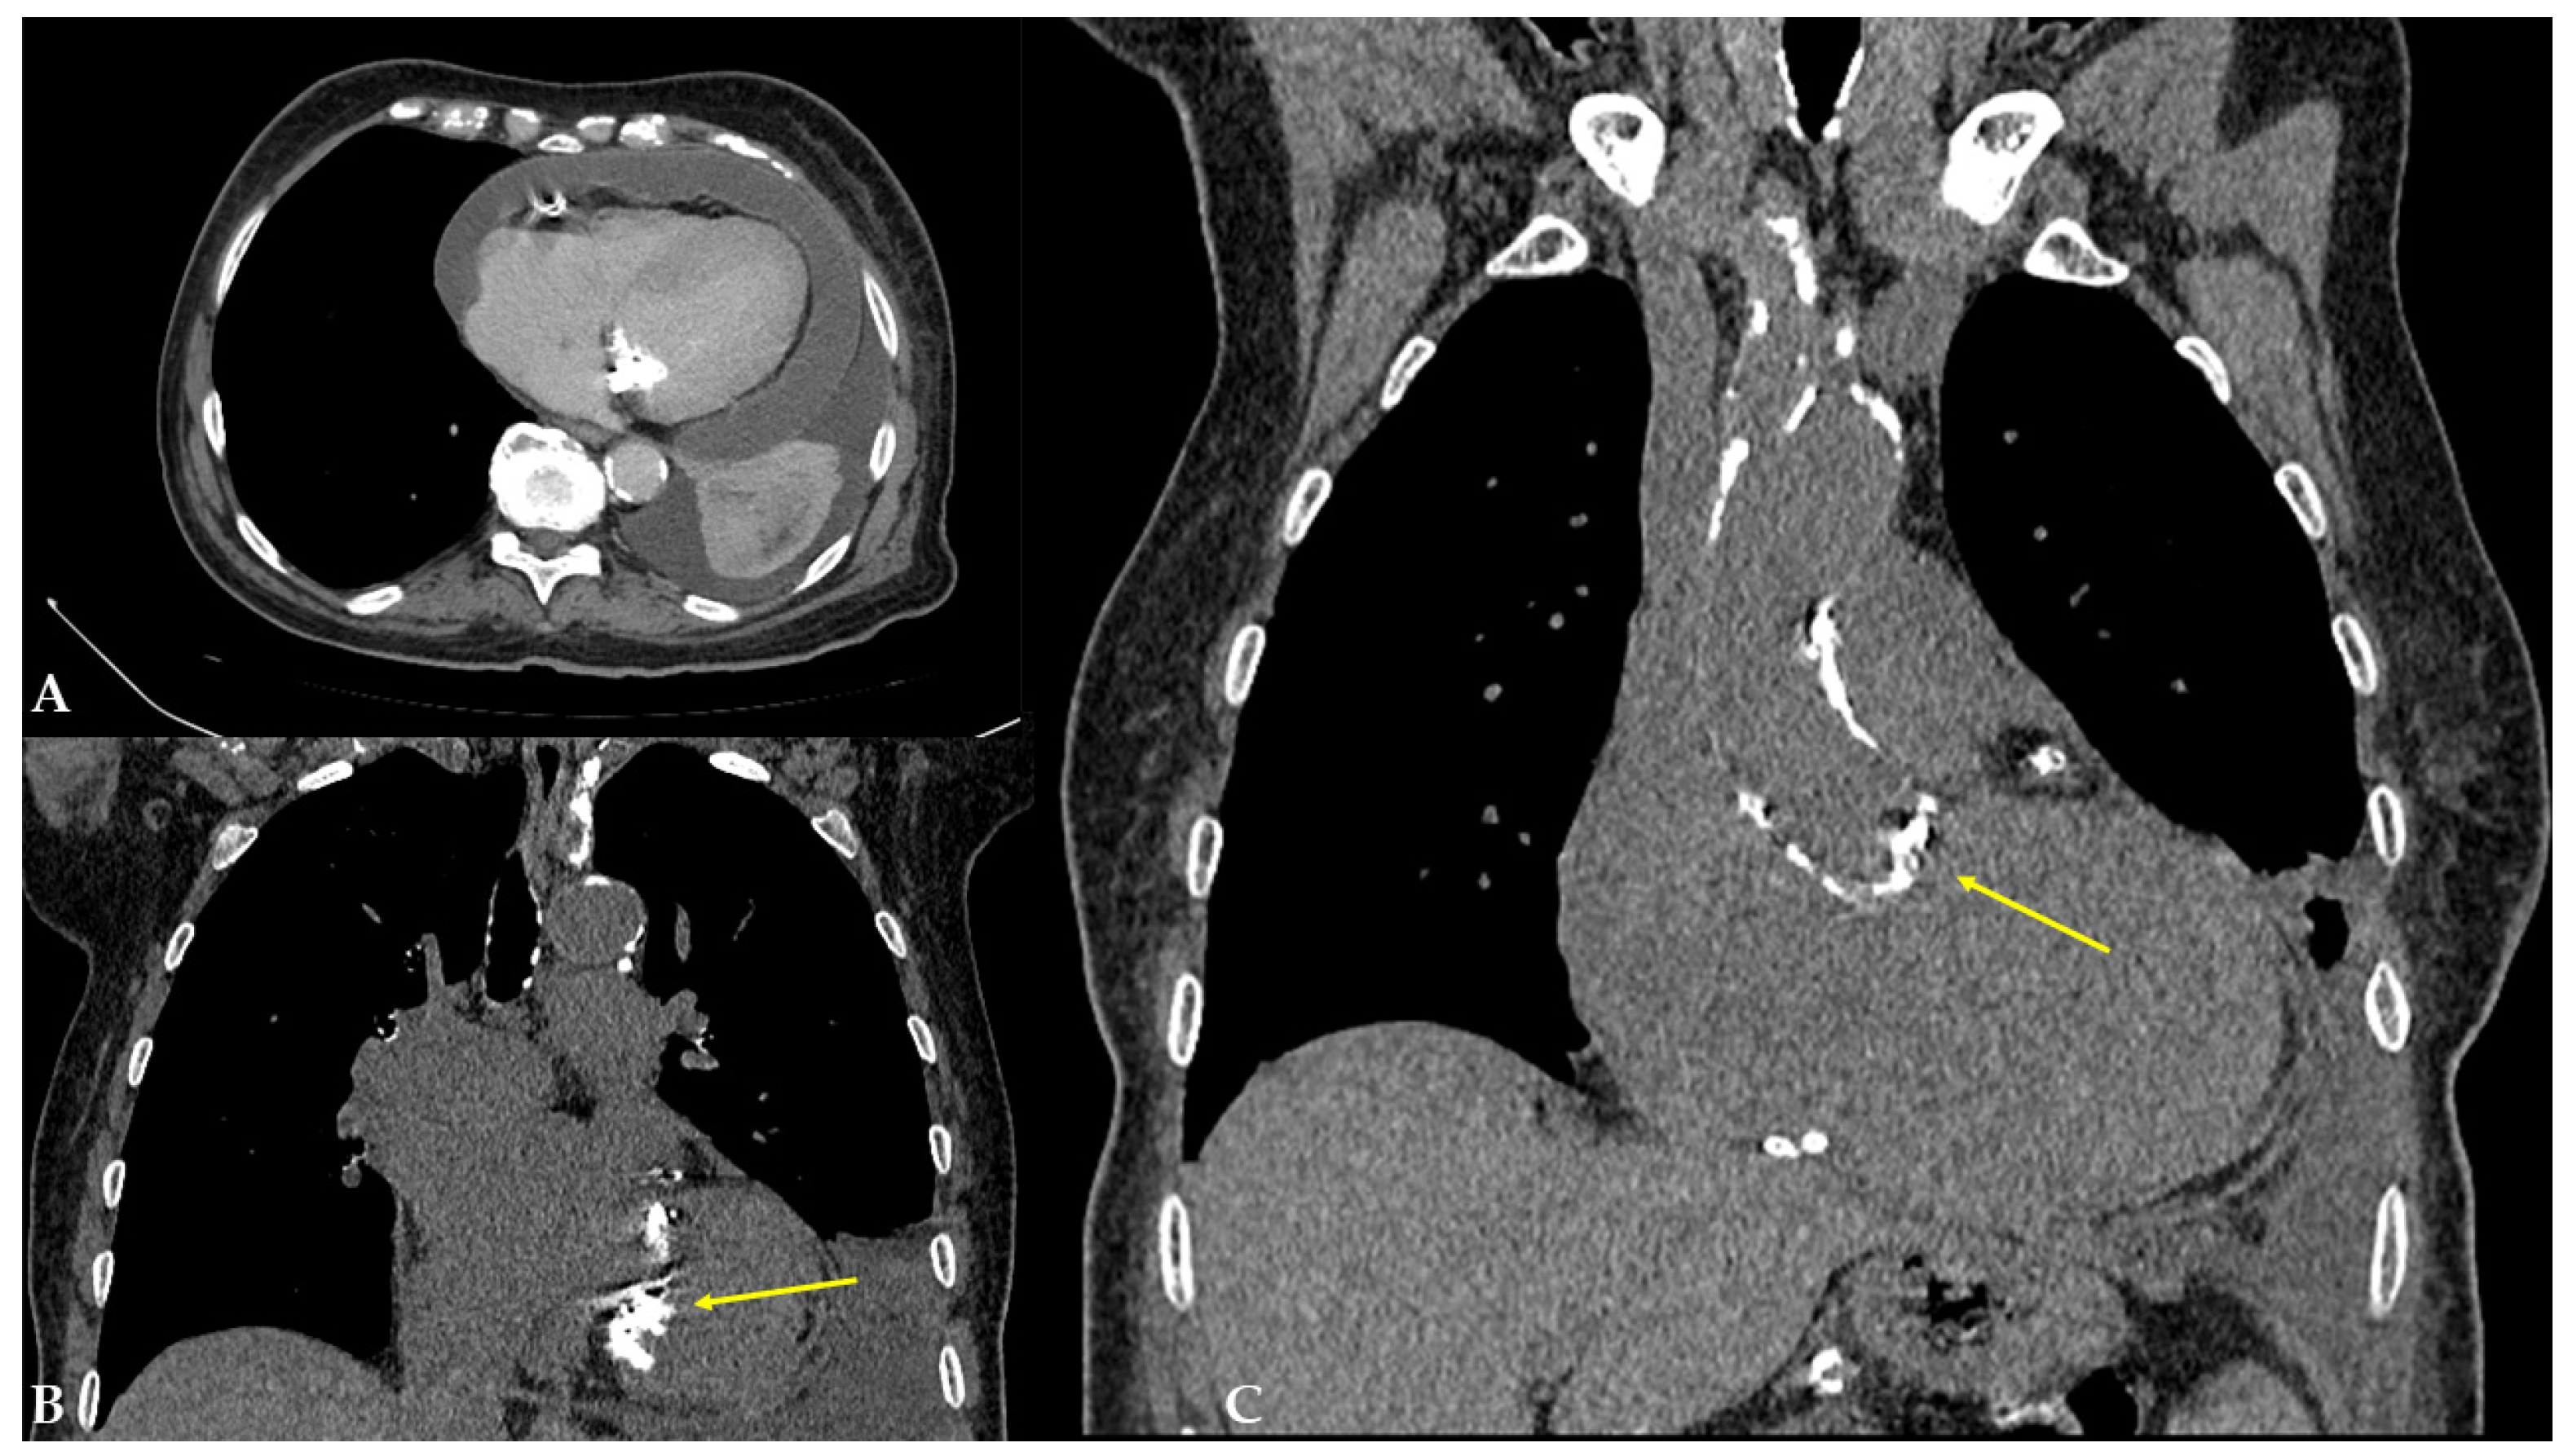

2. Case Presentation